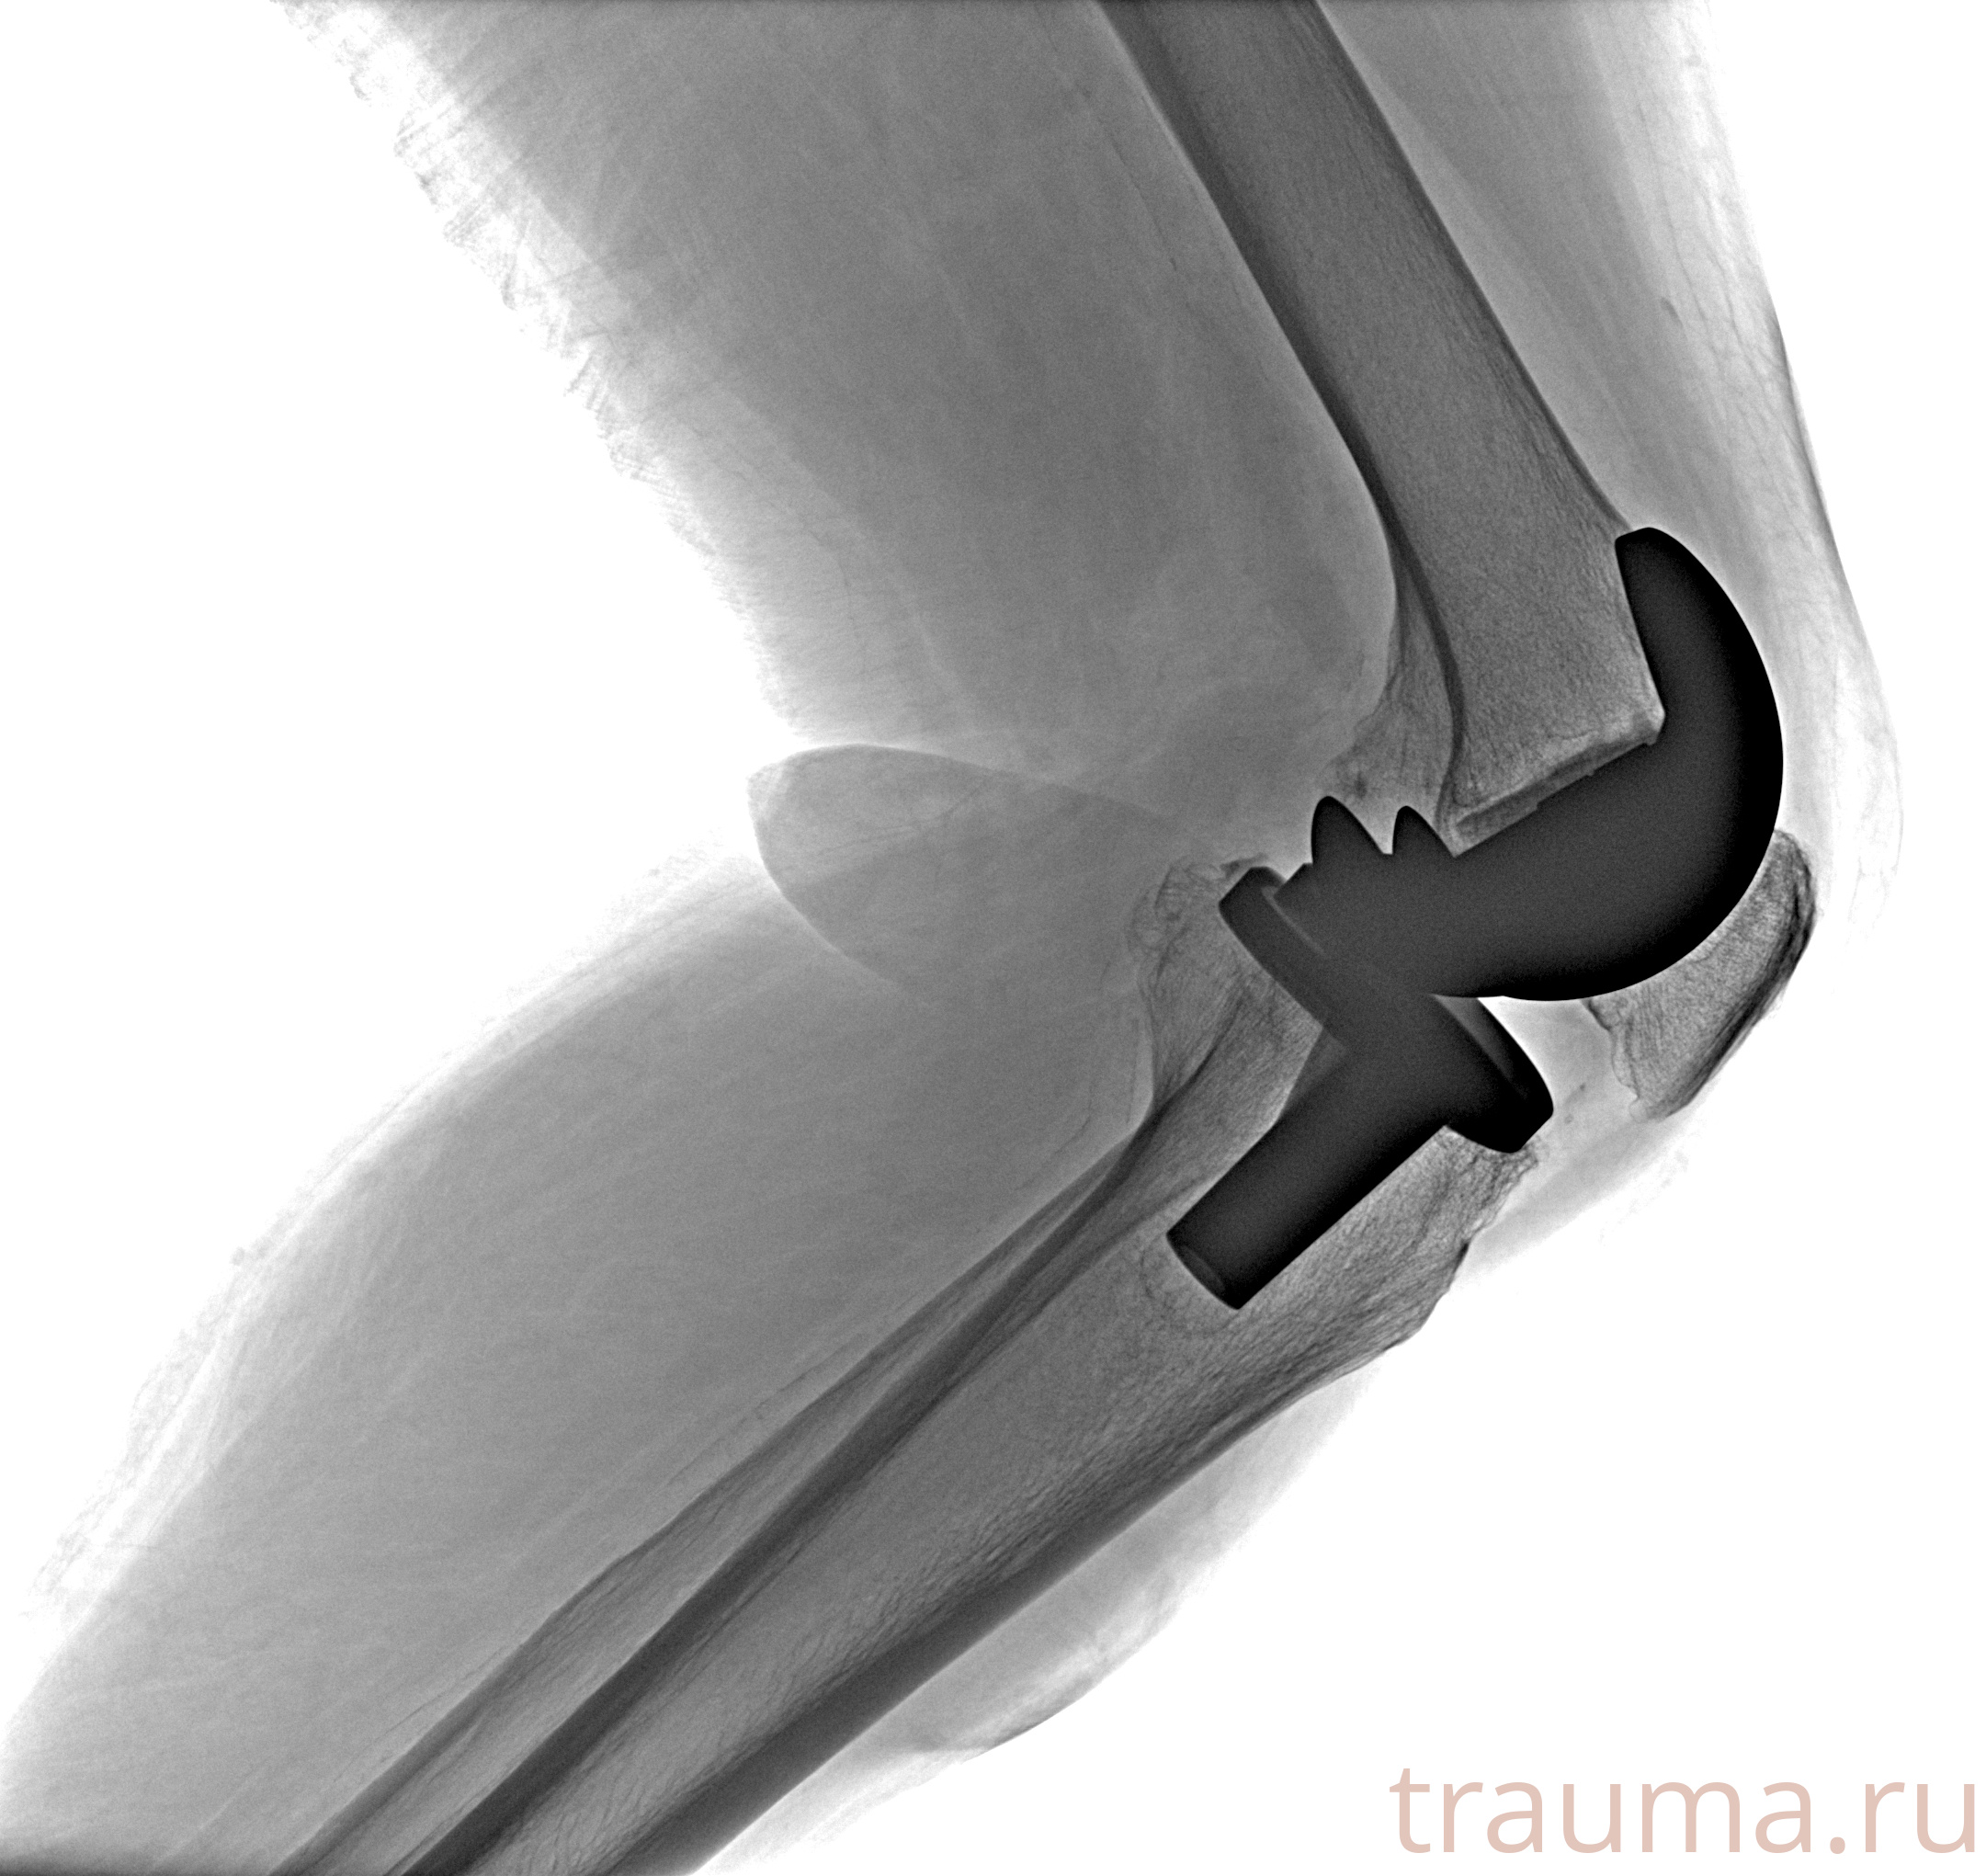

Рентгенограммы